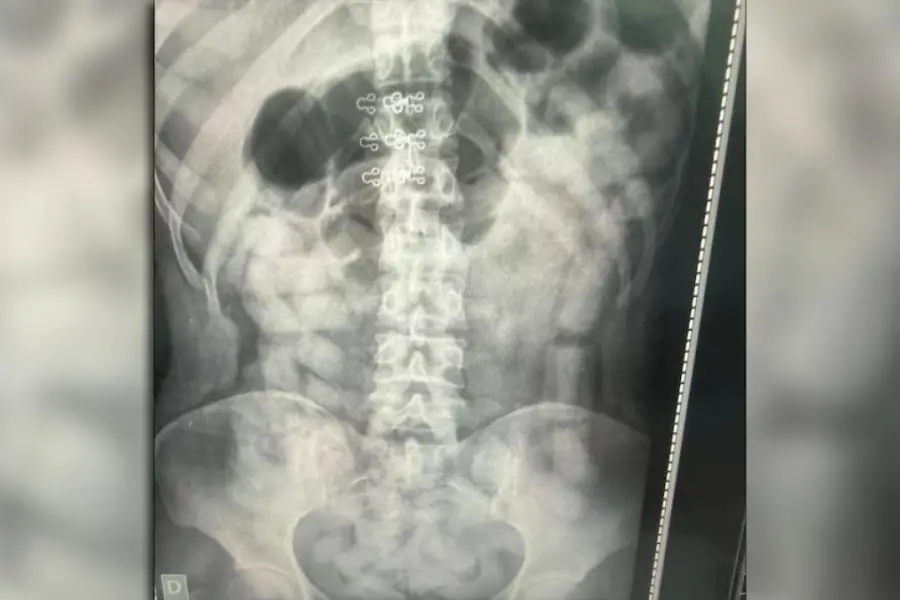

Bajo las órdenes del Juzgado Federal de Tucumán N° 2, los 53 pasajeros fueron trasladados para una revisión exhaustiva. A la mañana siguiente, las placas radiográficas confirmaron el peor escenario: cuatro mujeres y dos hombres tenían sus abdómenes repletos de cuerpos extraños.

Los involucrados fueron internados de inmediato en los hospitales de Santa Ana y Los Sarmientos. Allí, bajo estricta custodia médica y policial, expulsaron un total de 503 cápsulas. El riesgo de muerte por el estallido de un solo envoltorio es casi del 100%, pero en esta ocasión, el cargamento llegó a pesarse en su totalidad.